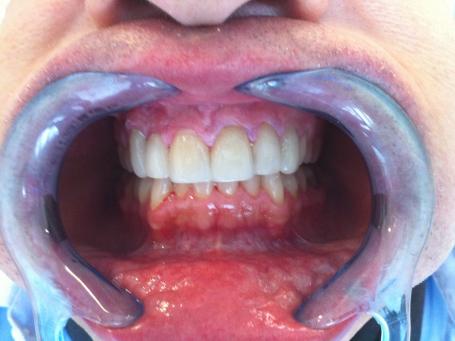

5°) Photo finale.

Pose des facettes céramique. Des aménagements occlusaux sont réalisés.l

6°) Facettes céramiques scéllées.

Ces facettes ont permis de restaurer le sourire avant tout....